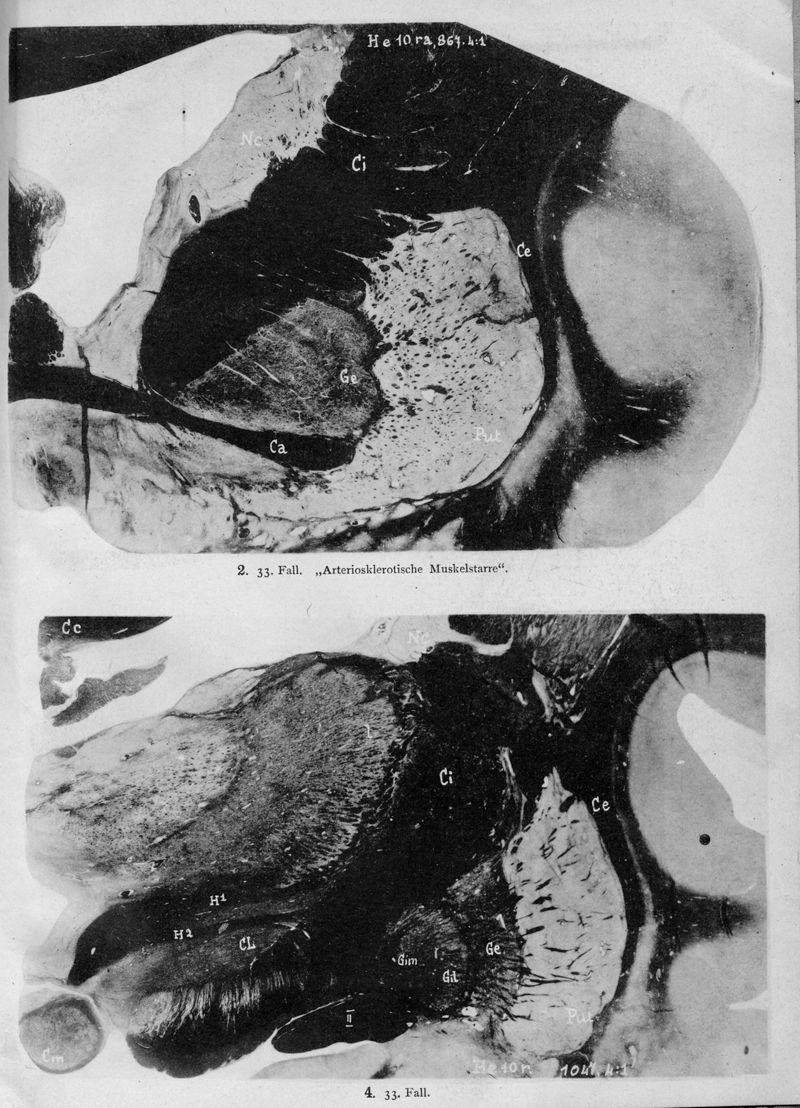

VOGT, Cécile / VOGT, O.

In : Journal für Psychologie und Neurologie,

1920, Vol. 25, pp. 627-846